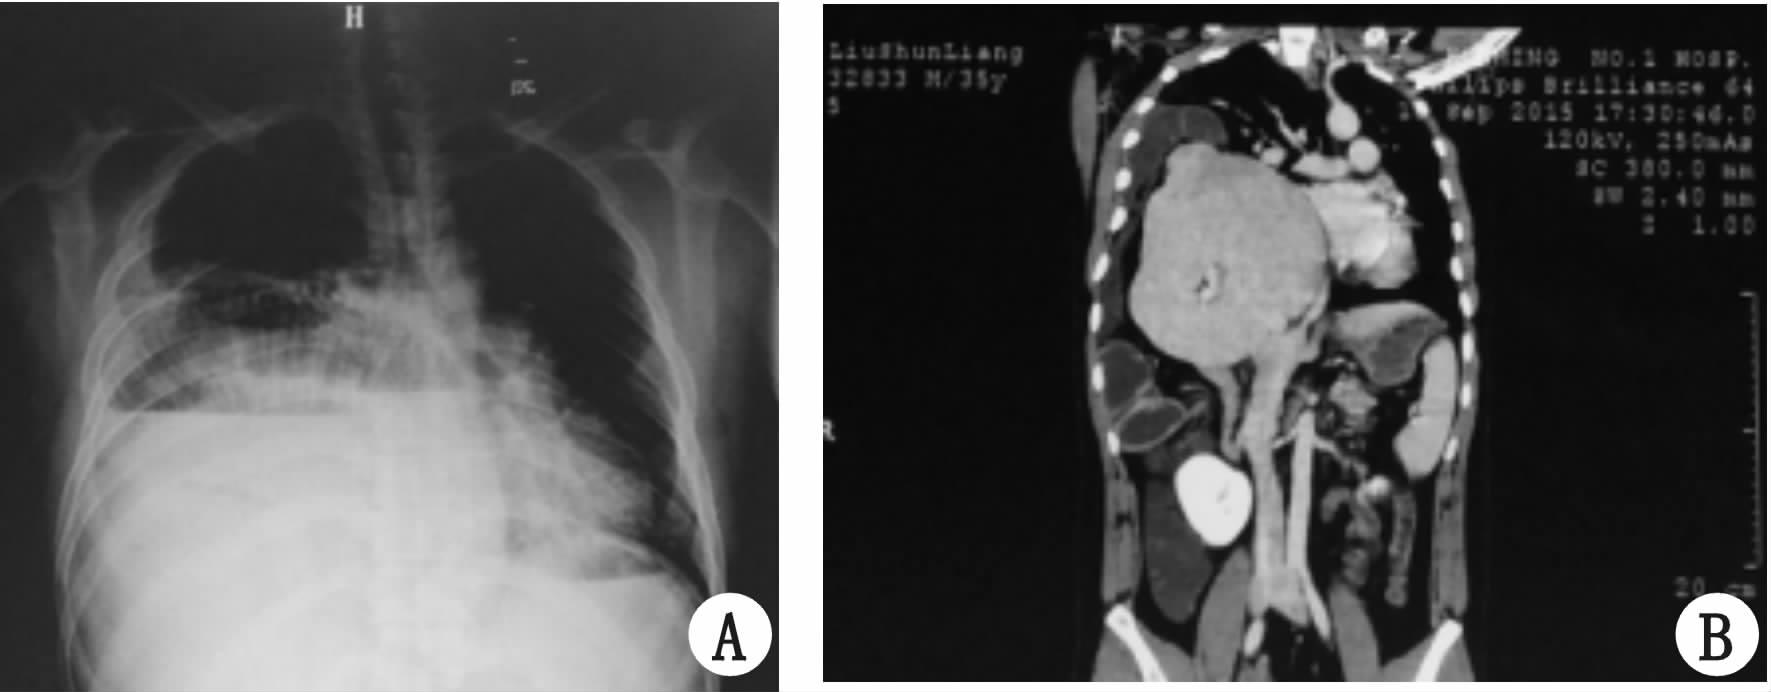

患者肝脏回纳腹腔后,腹腔压力上升,术后前5 d腹内压波动在12~25 cmH2O(1 cmH2O=0.098 kPa),合并腹腔间隔综合征,术后转氨酶、胆红素一过性升高,术后3周复查胸片及CT平扫示小肠,结肠,肝脏及右膈位置正常(图 3),术后27 d痊愈出院。

图 3 术后胸片(A)和CT(B)图片